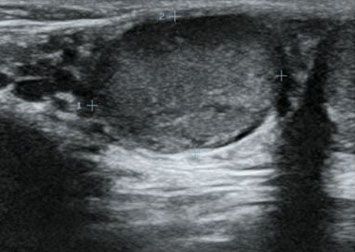

Case Report: We present a female with right perinephric abscess and reno-duodenal fistula secondary to a long-standing history of kidney stones. Treatment involved drainage of the abscess, nephrostomy tube placement, intravenous antibiotics, and open nephrectomy and duodenal repair with gastrojejunostomy.